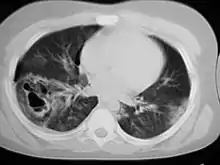

أفضل طريقة لتشخيص أكياس البنكرياس الكاذبة هي التصوير الطبقي المحوري. الكيس الكاذب يبدو بشكل عام ككتلة مليئة بالسوائل. وأحيانا تستخدم طرق أخرى للتمييز بين الأكياس العادية والأكياس الكاذبة،[4] مثل الأمواج فوق الصوتية بالمنظار أو سحب السائل بالإبرة الدقيقة.[6]

و يمكن استخدام طريقة تصوير الأمواج فوق الصوتية عبر البطن لتشخيص الأكياس الكاذبة ويبدو الكيس الكاذب في هذه الحالة على شكل ذي صدى، وتعزيز صوتي بعيد. تكون في الغالب مدورة ومغلفة بحائط رقيق. الأكياس الكاذبة تبدو بشكل أكثر تعقيد عندما تكون صغيرة في العمر، ويكون فيها نزيف، أوملتهبة. التصوير بالأمواج فوق الصوتية عبر البطن لديه معدل تحسس في كشف أكياس البنكرياس الكاذبة بنسبة 75%-90% ، مما يجعله أقل مرتبة من التصوير الطبقي المحوري الذي لديه معدل 90%-100%. [6]

التصوير الطبقي المحوري هو أكثر دقة، وتوفر تفاصيل أكثرعن الكيس الكاذب وما يحيطه. لكن نقطة ضعف التصوير الطبقي المحوري أنه ليس لديه القدرة على التميز بين الكيس الكاذب والورم التكيسي [الإنجليزية] بالإضافة إلى أنه من الممكن أن يؤدي إلى تدهور وظائف الكلية نتيجة تأثير المادة الملونة التي تعطى وقت التصوير الطبقي المحوري.[6] تصوير الرنين المغناطيسي ، و تصوير الرنين المغناطيسي للقنوات الصفراوية: هي طرق فعالة في كشف الأكياس الكاذبة، لكن لا تستخدم بشكل دوري؛ لأن التصوير الطبقي المحوري يوفر معظم التفاصيل المطلوبة. لكن هذه الطرق توفر تباين أفضل، وتوفر وصف أفضل لتجمعات السوائل، وتصوير بقايا الخلايا في تجمعات السوائل وكشف وجود النزيف.[6] وتصوير الأمواج فوق الصوتية عبر المنظار، توفر فحص ثانوي لتقييم أكبر للأكياس التي وجدت بفحوصات أخرى، وتستخدم لتحديد هل هذه أكياس كاذبة أم لا.[6]